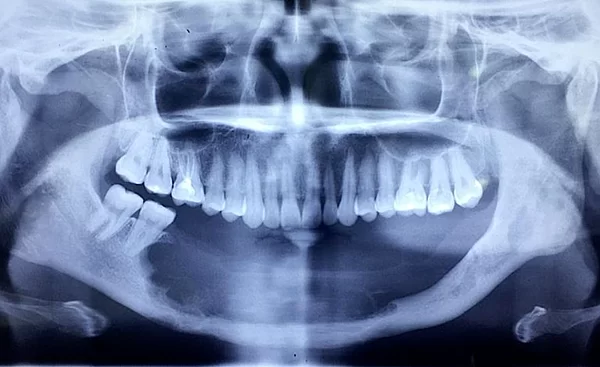

Ngay khi bạn có nhu cầu trồng răng Implant để thay thế cho các răng đã mất, các bác sĩ sẽ tiến hành khám lâm sàng và lập kế hoạch điều trị. Tại Kubet Worldwide, bạn sẽ được chụp phim X-quang kỹ thuật số 3D bằng máy Cone beam CT để đánh giá tổng thể cấu trúc xương hàm theo 3 chiều không gian như xương có bị thiếu không, cấu trúc giải phẫu, hệ thống dây thần kinh liên quan…